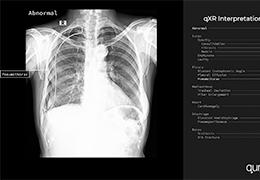

分析智能。

这些功能利用数字控制面板分析运营、业务和临床绩效。

使管理员能够跟踪关键参数,包括平均曝光率、拒绝的影像和探测器统计信息。

帮助确定需要改进的方面,支持为员工和部门制定适当的改进计划。